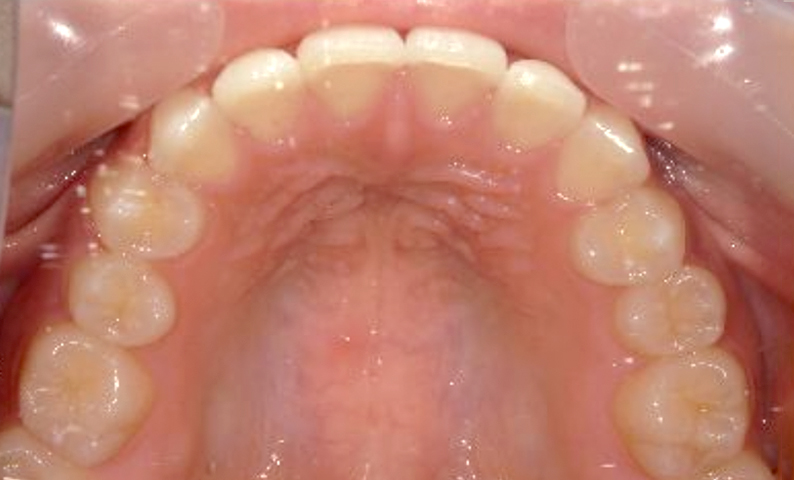

症例:上下顎の部分矯正

症例_002 前歯「捻転歯」症例

治療期間:10ヶ月金額:54万円+税30代女性少しのねじれ捻転歯前歯の突出感

| Before | After |

|---|---|

|